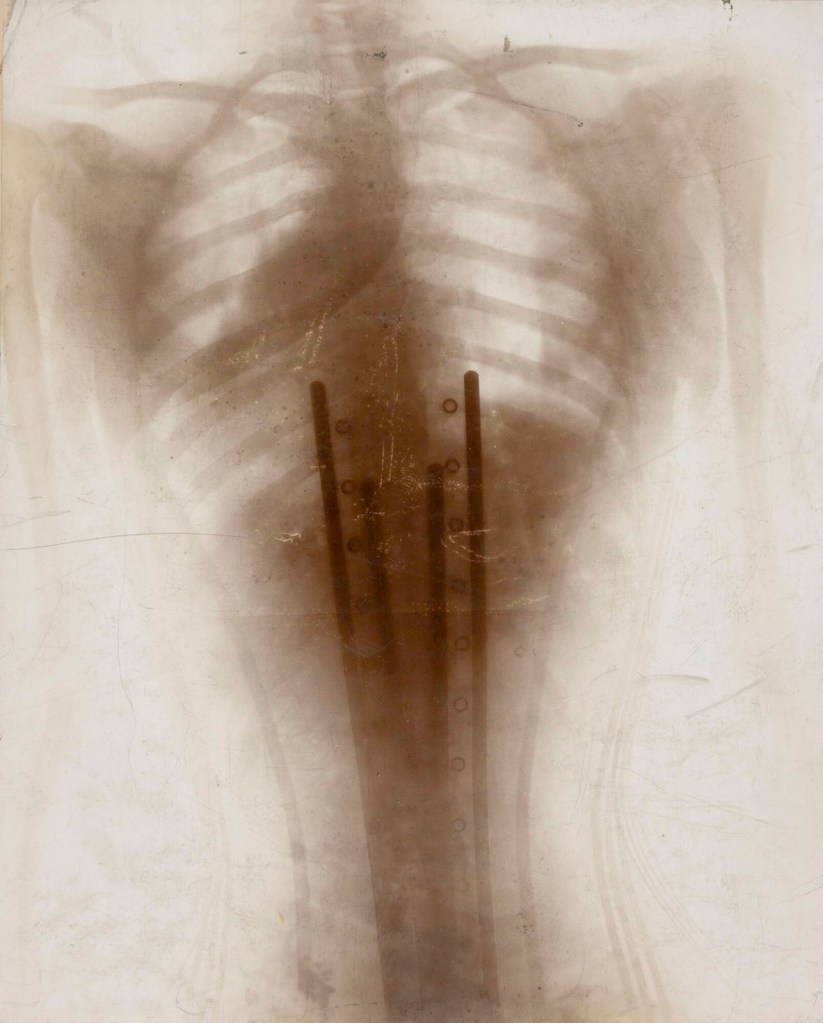

Henri Van Heurck (Belgian, 1838-1909) 'X-ray of chest deformed by corset' 1896-1897

Henri Van Heurck (Belgian, 1838-1909)

X-ray of chest deformed by corset

1896-1897

Daylight gelatin silver print

Collection GUM – Ghent University Museum

Henri Ferdinand van Heurck (28 August 1838 – 13 March 1909) was a Belgian diatom specialist and microscopist. Born in an industrialist family, he taught himself microscopy and botany and wrote several pioneering works on diatoms, their study under the microscope and their preservation. He pioneered the use of electric lighting and its use in microphotography.